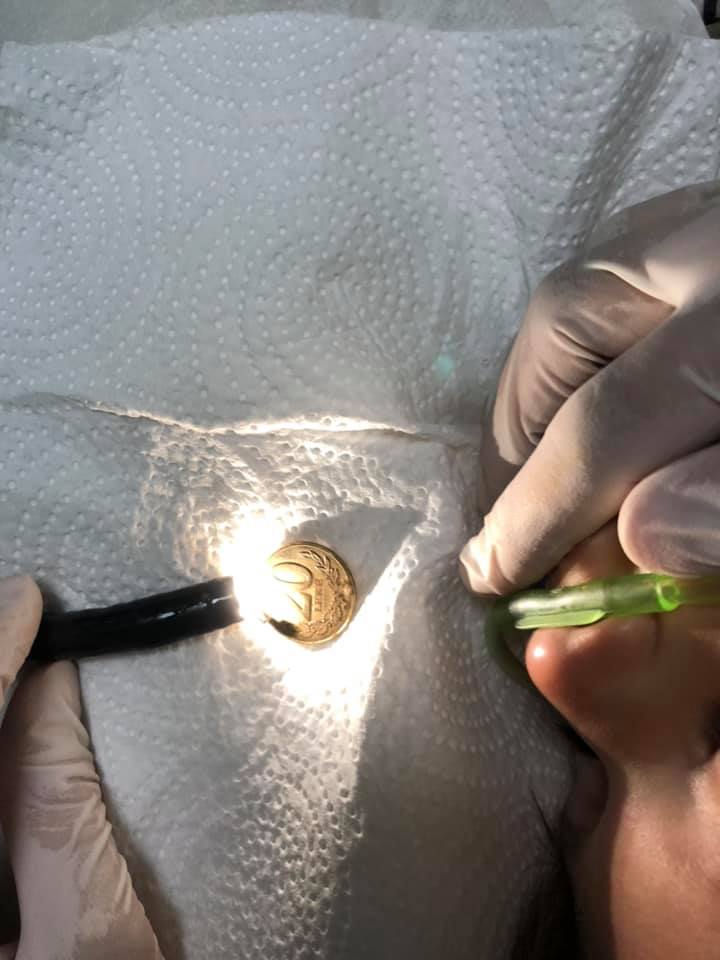

Pak pas mesnate familja e kishte dërguar fëmijën e tyre tek doktori pasi kishte gëlltitur një monedhë 20 lekë të Shqipërisë. Monedha ka përfunduar në ezofag dhe ia ka vështirësuar frymëmarrjen 2-vjeçarit.

Mjeku Besnik Elezi nga Gjilani ka njoftuar për këtë ndërhyrje të tij tek fëmija, madje edhe ka shpërndarë fotografi, ku edhe shihet monedha në vlerë të 20 lekëve.